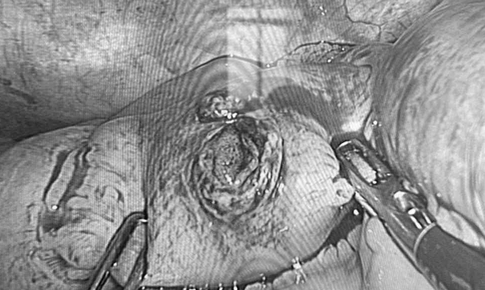

SKĐS - Các bác sĩ Bệnh viện Hữu nghị Việt Nam–Cuba Đồng Hới đã phẫu thuật cấp cứu thành công một trường hợp là nam thanh niên bị súng bắn đinh bắn xuyên thành bụng, găm thủng ruột non trong lúc lao động.